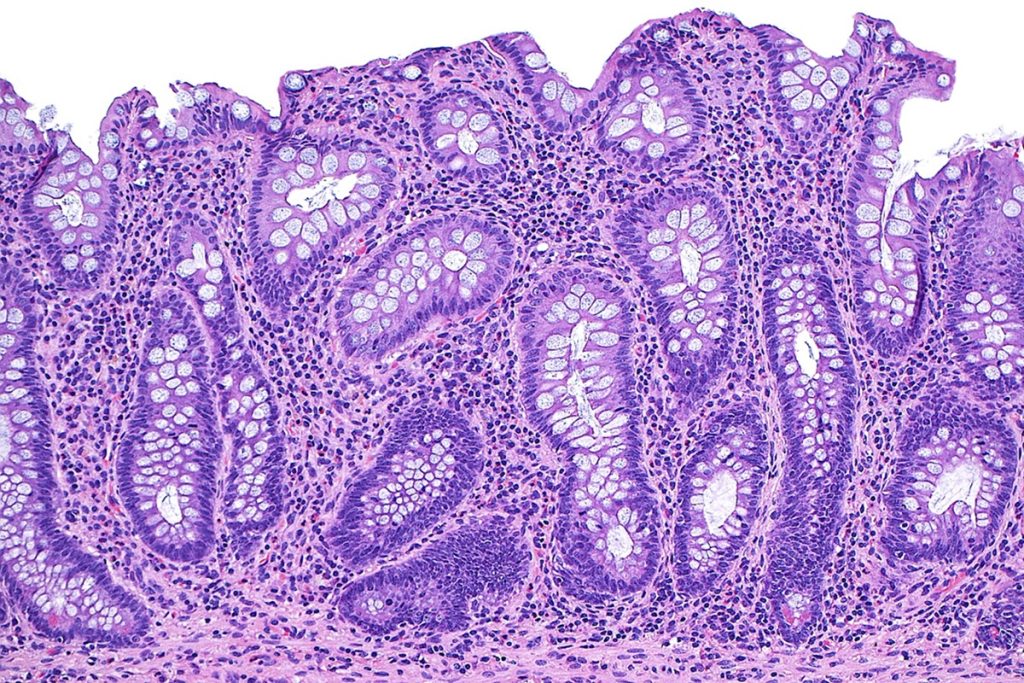

Divididas basicamente entre doença de Crohn (em todo o aparelho digestivo) e retocolite ulcerativa (no cólon, a porção final do intestino), as condições causam inflamação crônica do intestino e podem desencadear úlceras. Ainda não se sabe exatamente como as DIIs se desenvolvem, mas pesquisas sugerem que a flora intestinal pode desencadear uma reação imunológica em pacientes com predisposição genética.

“O objetivo é que, ao fazer uma biópsia, ultrassom ou endoscopia, não se encontre doença ativa. Não basta se sentir bem, é importante estar bem”, explica a diretora de assuntos médicos em imunologia para a América Latina Tatiana Deschamps, da Johnson & Johnson.

O estudo mediu resultados endoscópicos e histológicos, que mostram respostas mais profundas ao tratamento, indo além da remissão dos sintomas. Os benefícios foram observados para regimes subcutâneos de 100 mg a cada 8 semanas e 200 mg a cada 4 semanas.